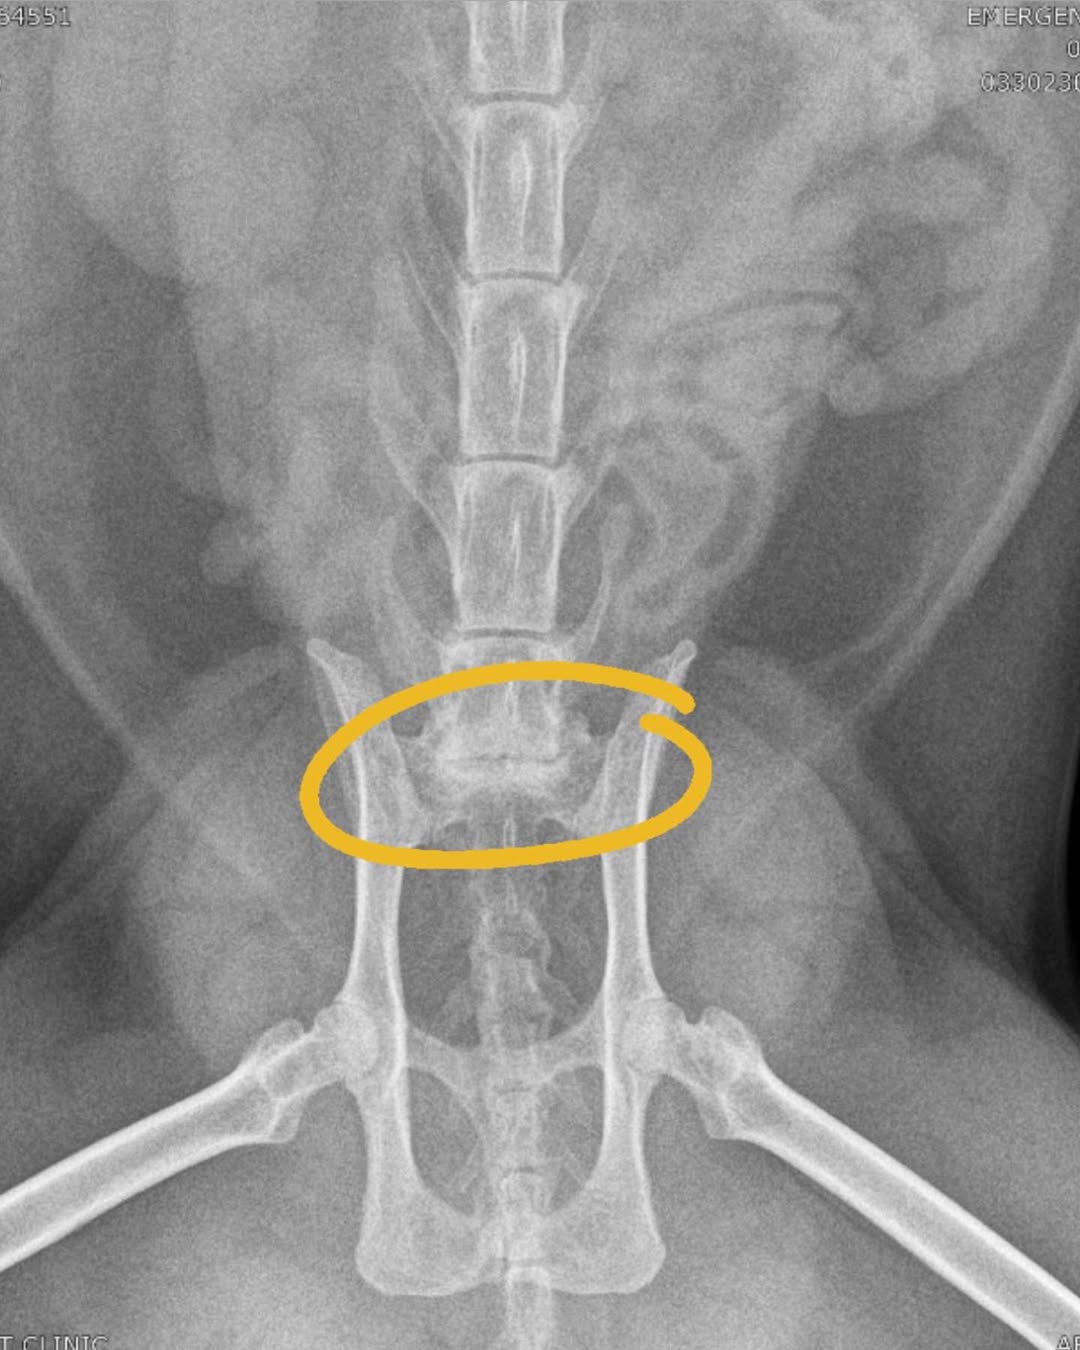

Durante o período em que vivia com a família temporária, ele começou a apresentar dores persistentes na região lombar.

Exames iniciais levantaram a hipótese de uma antiga lesão, mas a tomografia computadorizada revelou um quadro diferente.

O diagnóstico apontou sinais de uma doença degenerativa, que poderia limitar parte de seus movimentos e causar desconforto contínuo.

A gravidade do problema mobilizou ainda mais a rede de apoiadores que já acompanhava sua história.

Então a recomendação médica foi dar seguimento a novos exames, incluindo uma ressonância magnética, para compreender melhor a condição.

Surgiu uma possibilidade de cirurgia, mas com chances incertas de sucesso.